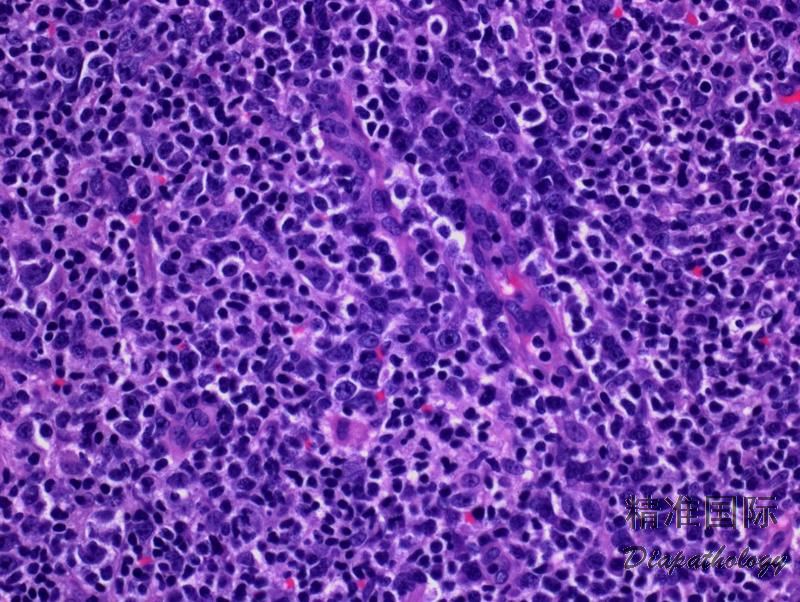

- 淋巴结结构部分或完全破坏,多形性细胞弥漫侵润,常延至结外组织,但常不累及胞膜下窦。有时侵润位于残存滤泡周围或滤泡间。除异型淋巴细胞外,还有反应性细胞如嗜酸性粒细胞、浆细胞、组织细胞等。此外,背景中有大量、常呈分支状的毛细血管后高内皮静脉增生。

- 肿瘤淋巴细胞一般小到中等,也有散在大细胞。细胞核圆形或不规则,胞质透明,细胞膜清晰,常松散聚集成小灶状或融合成片。也可见散在免疫母细胞和偶尔 HRS 样细胞。

- 常有三种相互重叠生长模式:1)滤泡增生且结构基本完整,肿瘤细胞沿滤泡周围生长(其表达辅助 T 细胞抗原可与反应性滤泡增生鉴别);2)仍有残存滤泡,但萎缩变小,肿瘤细胞扩展到副皮质区;3)淋巴结结构完全或几乎完全破坏,残存滤泡或许偶见于显著增生扩张的副皮质区外周。